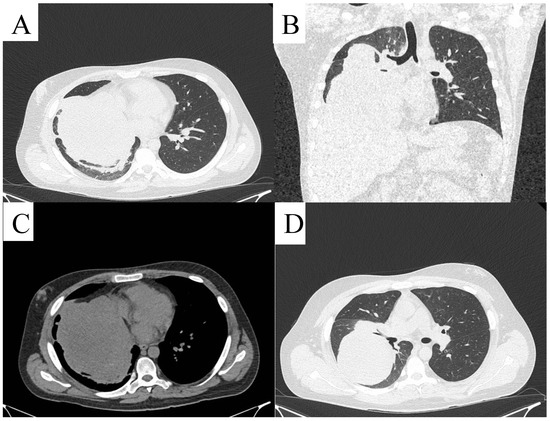

| 13 | Presented case | M/24 | Dyspnea, heartburn, intermittent tachycardia, right shoulder pain, expectoration of white sputum | Left lateral retroperitoneal region | 22 × 13 | Surgery, Trametinib treatment | NR |